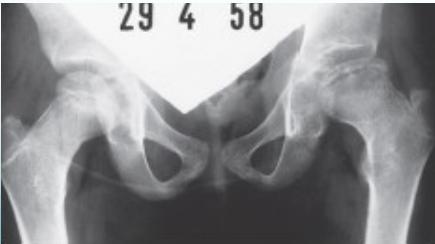

Radiographic Stages:

-

Initial/ Bone Death Stage - May initially appear normal on x-ray

- Increased density followed by collapse

Revascularization and Repair Stage - Reduced density and fragmentation on x-ray

Distortion and Remodeling Stage - Distortion, flattening (coxa plana)

- Enlargement (coxa magna) with partial uncoverage

Radiological Progression:

Progression: Sclerosis → Collapse → Fragmentation → Remodeling

Imaging Examples: